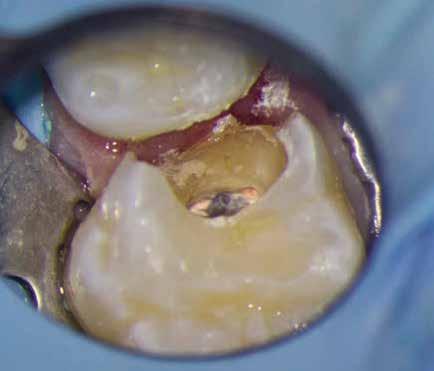

1. a–g. ábrák: A direkt pulpasapkázás lépései. Kiindulási bitewing-felvétel: A meglévő restaurátum közel helyezkedett el a pulpakamrához (a). Kiindulási periapicalis felvétel: Nincs periapicalis elváltozás fennállására utaló jel (b). A pulpaexpozíció (c). A vérzéscsillapítás céljából 20 másodpercen keresztül steril vattagombóccal történő kompressziót követően látható pulpaseb (d). A pulpasapkázás céljából behelyezett anyag, a széli részek tisztázása előtt készült felvétel (e). A röntgenárnyékot nem adó ideiglenes tömés behelyezése után készült felvétel (f). Az első ülés végén a röntgenárnyékot nem adó ideiglenes töméssel ellátott fogról készített röntgenfelvétel (g).

Esetbemutatás (1.)

A diagnózisunk reverzibilis pulpitis volt. Periapicalis elváltozás jelenlétét nem vélelmeztük. A fogban lévő amalgámtömés eltávolítása során körülbelül egy 3 mm átmérőjű pulpaseb keletkezett a buccalis pulpaszarvnak megfelelően (1. a–g. ábrák) Mivel nem tapasztaltunk jelentős vérzést, és a diagnózisunk reverzibils pulpitis volt, ezért a direkt pulpasapkázás elvégzése mellett döntöttünk.

A kavitást 2,5%-os nátrium-hipoklorit oldattal fertőtlenítettük, majd sűrű konzisztenciájú kalcium-szilikát alapú anyagot (CeraPutty, Meta Biomed) készítettünk elő a direkt pulpasapkázás elvégzéséhez. Az első kezelés végén röntgenárnyékot nem adó ideiglenes töméssel (NexTemp LC, Meta Biomed) zártuk

az üreget annak érdekében, hogy a direkt pulpasapkázásra használt anyag megfelelő pozícióját radiológiailag ellenőrizni tudjuk. A második ülés során kompozit tömőanyagból (Ezfil, Meta Biomed) direkt adhezív restaurátumot készítettünk.

A kezelést követően a beteg tünetmentes volt. A kérdéses fog a kontrollvizsgálatok során végzett szenzibilitástesztekre fiziológiás reakciókat adott. A hat hónapos kontroll alkalmával készített röntgenfelvételen a sérülésnek megfelelően széles dentinhidat észleltünk (2. ábra). A restaurátum a hároméves kontroll során is megfelelőnek bizonyult (3. ábra)